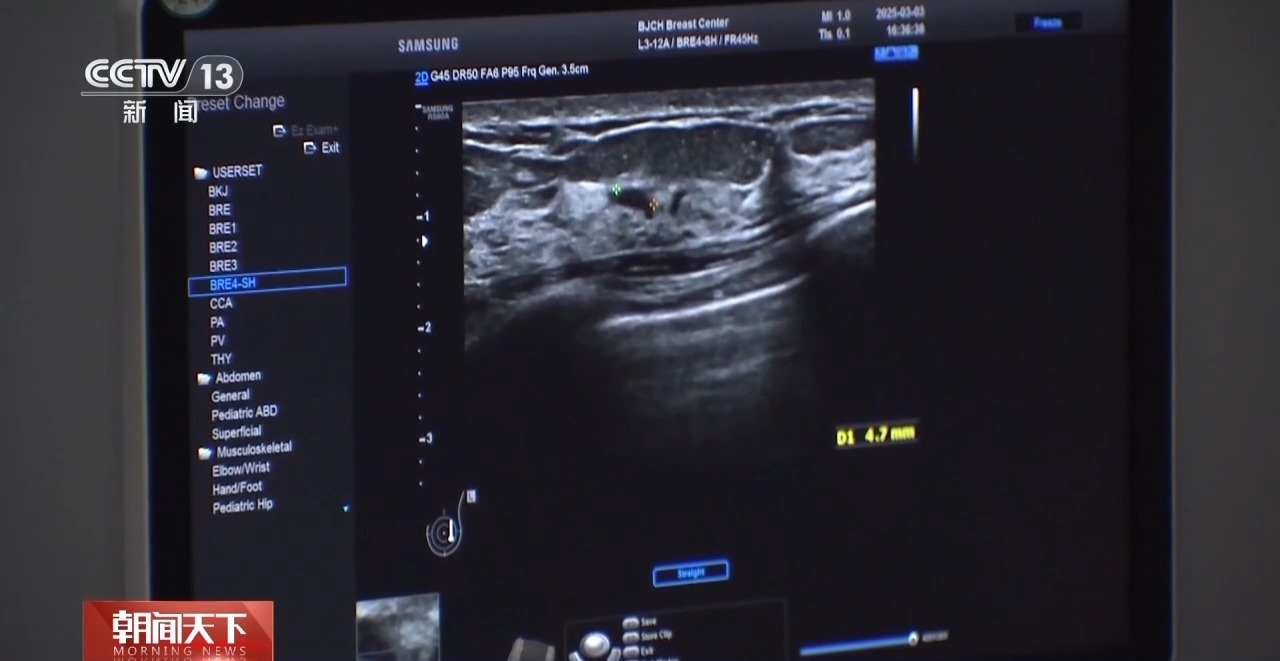

北京大学肿瘤医院乳腺癌预防治疗中心主任医师范照青:一般来说我们推荐40岁以上的女性,1到2年做一次钼靶摄影,也推荐女性朋友每年至少做一次乳房的超声检查。钼靶检查有可能会发现极早期的乳腺癌,也就是说所谓的原位癌,它一般还没有发展成浸润癌的时候,是不会造成转移的,也就是说不直接威胁生命的阶段,我们把它发现及早处理掉。

钼靶和超声,是目前我国乳腺癌筛查的主要检查方法。两项检查,各有优劣,40岁以下的女性,一般来说,更适合做超声检查。

北京大学肿瘤医院乳腺癌预防治疗中心副主任医师霍苓:(超声检查)首先是没有辐射,然后安全性好,所以不同年龄阶段的女性,年轻女性孕妇,还有需要频繁检查的女性都是可以经常做的。钼靶是一个X线检查,它是有辐射的,做的时候会把病人的乳房整个夹成一个片状,所以病人的耐受程度也会差一点。

虽然超声没有辐射,但对于微小钙化,钼靶检查的敏感性更高。

根据国际通行的BI-RADS分级标准,对结节予以0至6级分类。专家表示,3级以上的结节,女性需要重视,按时复查或尽快就诊。

北京大学肿瘤医院乳腺癌预防治疗中心副主任医师霍苓:3级,一般半年要进行重复的超声检查;4级相对来讲恶性风险跨度比较大,一般建议要穿刺活检;5级的话就是高度怀疑恶性,所以一定要穿刺明确诊断,进行后续的治疗;6级就是已经在其他地方穿刺确诊为乳腺癌的病灶。